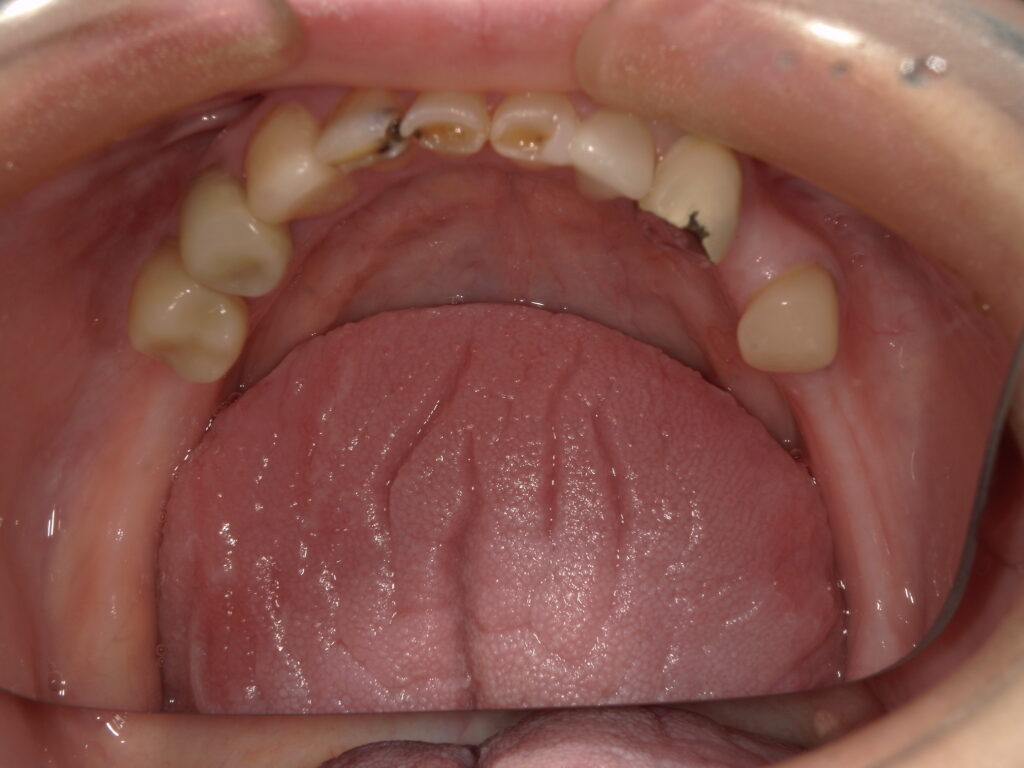

診査の結果、上顎は4本の歯を保存することが可能でした。

下顎は前歯9本を残すことができましたが、神経のない歯が多く、負担を分散する治療が必要な状態でした。

上顎は4本の歯を利用したレジリエンツテレスコープ。

下顎も同様に、神経のない歯が多いため、レジリエンツテレスコープで治療を行うことになりました。